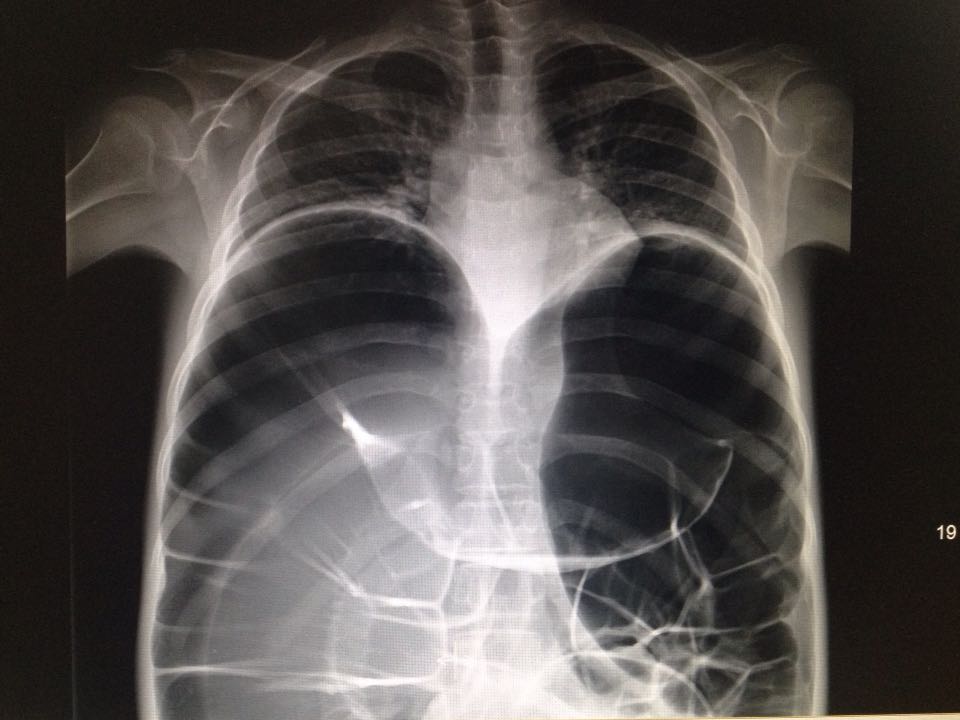

惊呆了!你可能未见过的片子。

19岁男孩 间断腹痛2年 如图,猜猜什么病?

不完全肠梗阻

肝癌

畸胎瘤

先天性巨结肠

克罗恩病